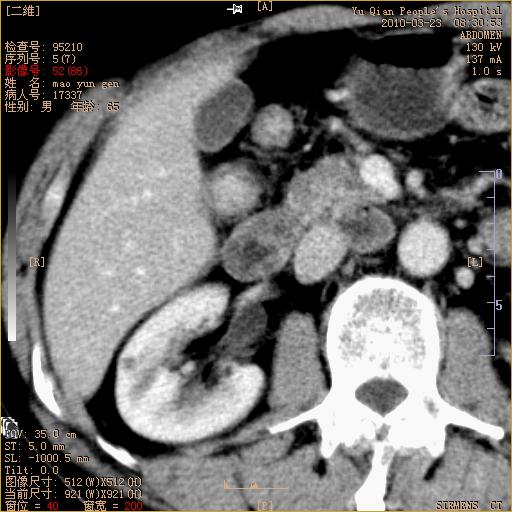

标题: CT25266:消瘦月余,前来肝部检查,请看看肠腔 [打印本页]

标题: CT25266:消瘦月余,前来肝部检查,请看看肠腔

肝区结肠占位,腺癌可考虑,建议肠镜活检。

升结肠肠壁增厚,不均强化,考虑升结肠腺癌可能性,建议肠镜检查。

1)考虑升结肠癌。2)右肾小囊肿。